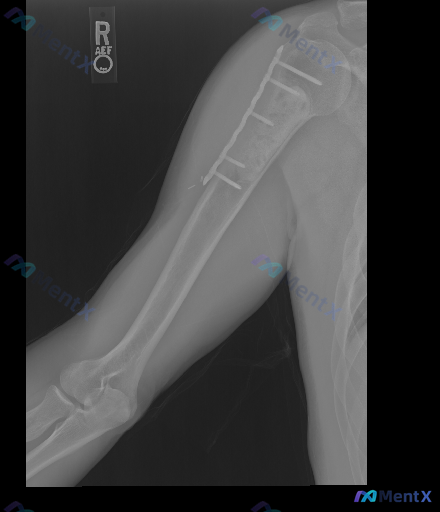

右肱骨近端术后复查X光片:骨折线清晰+断端间隙,第一步怎么考虑?

整理到一张右侧上臂(肱骨)正位X光片的影像资料,先不说结论,只看描述大家第一眼怎么考虑?

- 右肱骨近端有金属接骨板+螺钉固定,位置总体在位,未见明显断钉/松动脱出

- 接骨板下方肱骨干近段:骨皮质不连续,可见清晰骨折线,断端之间有明显间隙,还有轻度骨吸收

- 肩关节、肘关节对位基本正常

- 骨折周围局部骨密度减低(斑片状),考虑废用性脱钙可能

- 未见明显溶骨性/成骨性肿瘤样破坏,未见明显软组织肿胀/积气/脓肿